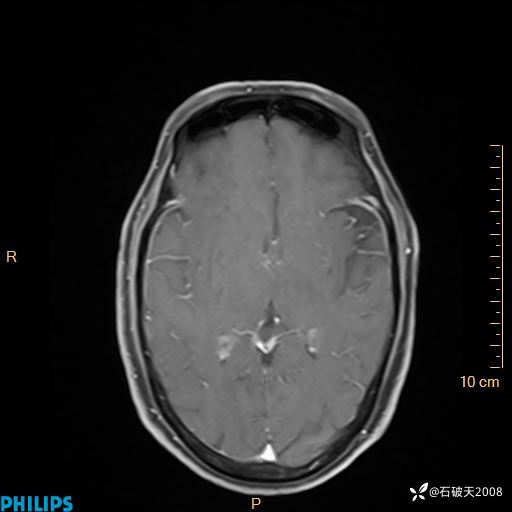

2024.2.21MR

增强轴位